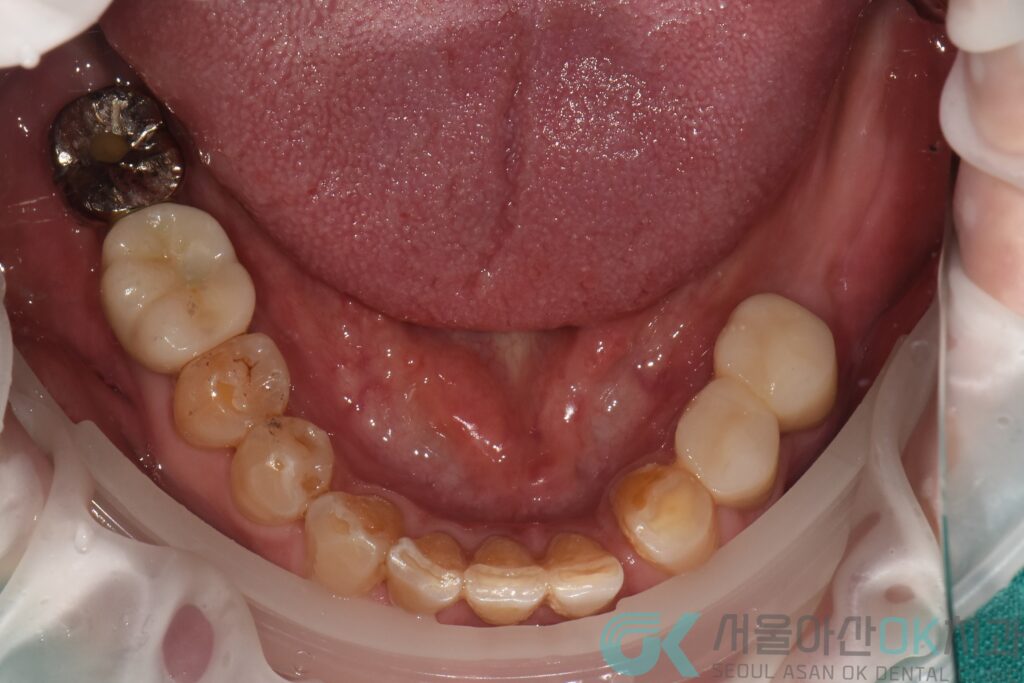

첫 번째는 잇몸부터 안정시키는 과정이었습니다.

치석 제거와 치주 치료를 통해

잇몸 속 염증을 가라앉히고,

치아를 지탱하는 환경을 먼저 정리했습니다.

잇몸이 흔들리면

임플란트도, 크라운도

결국 오래 버티지 못하기 때문입니다.